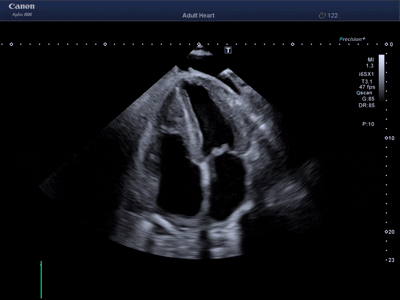

Transtorakalna ehokardiografija (TTE)

Ultrazvučna procjena srčane funkcije i strukture.

Standardni prikaz rada srca

Analiza srčanih kavieta i valvula

Funkcionalna analiza pojedinih srčanih segmenata